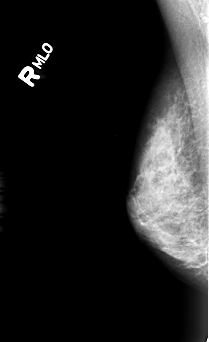

B_3005_1.RIGHT_MLO

RIGHT_MLO LINES 4440 PIXELS_PER_LINE 2712 BITS_PER_PIXEL 12 RESOLUTION 50 NON_OVERLAY